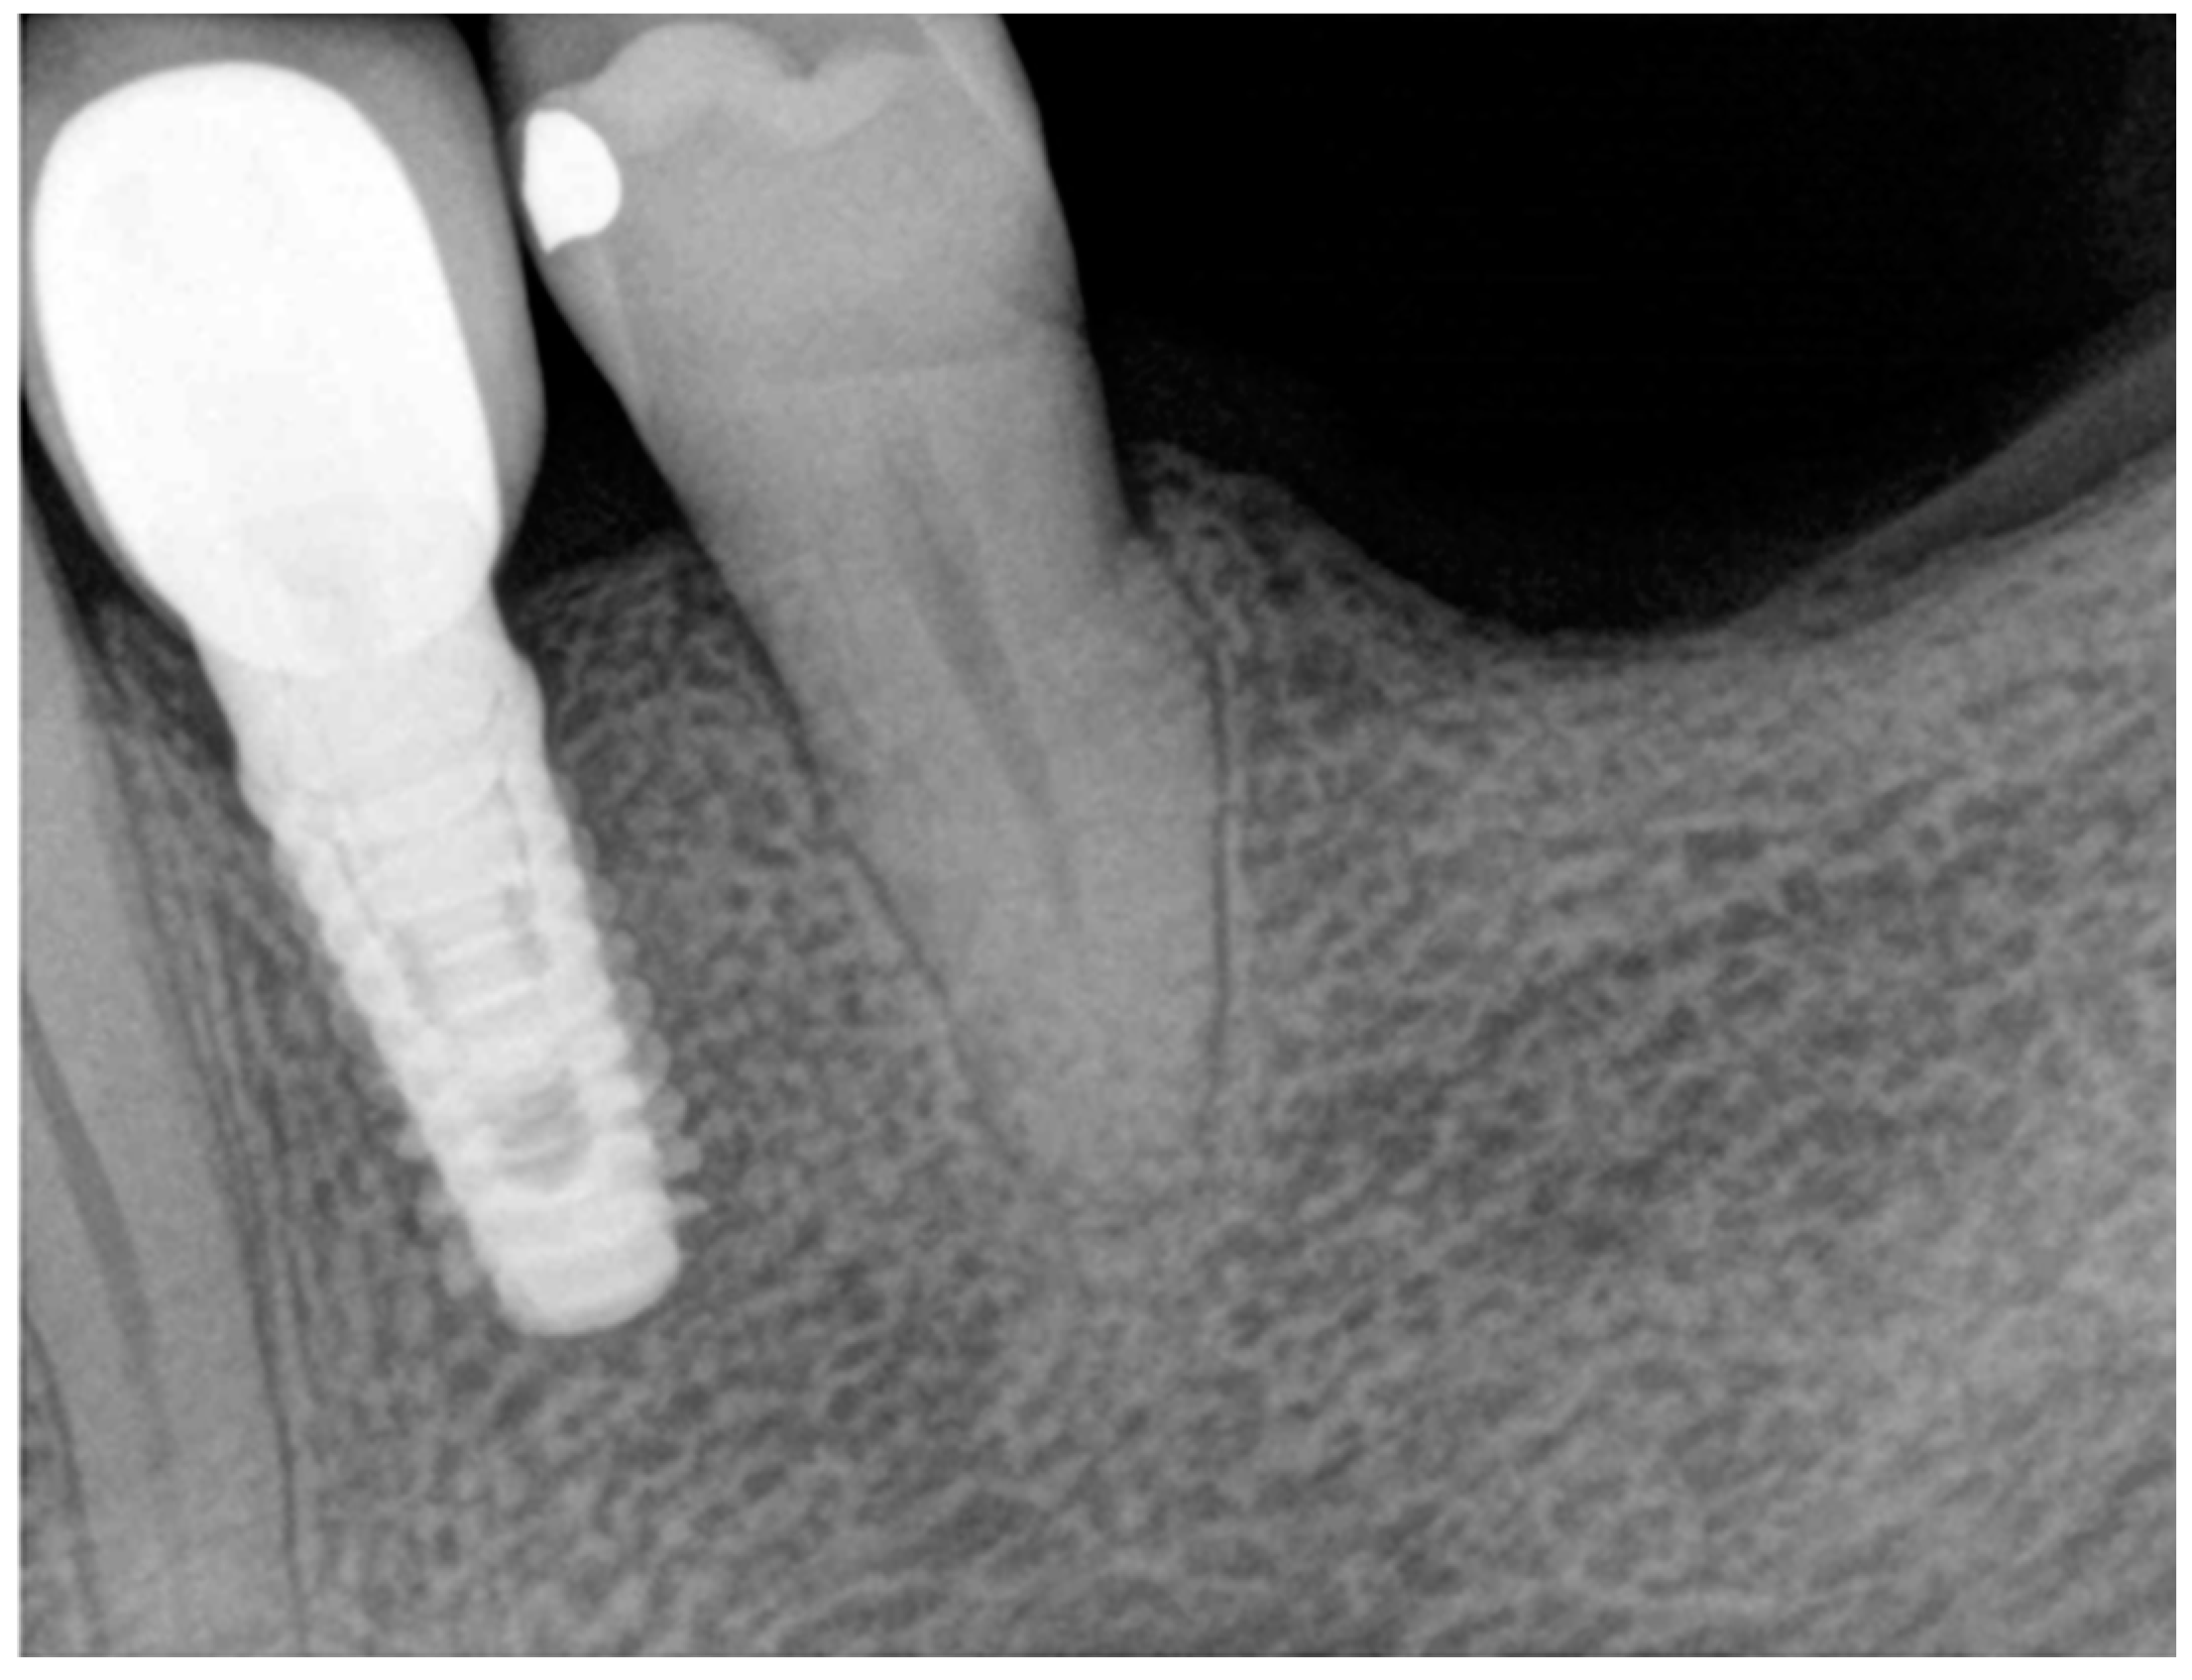

At the end of the work, a control endoral RX was carried out (Figure 8).

Figure 8. Final endoral RX.